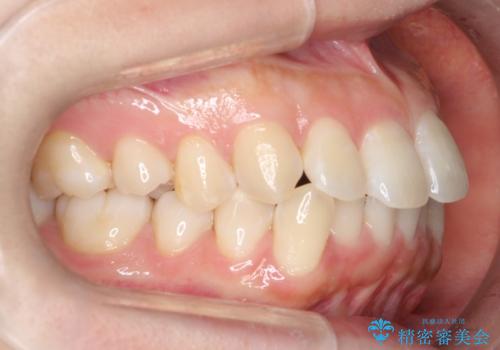

- 口元をさげたいという主訴で来院されました。4番の歯を4本抜歯し、審美装置にて治療をしました。

抜歯をしたことで口元の突出感が改善しました。約2年を予定していた矯正ですが、約1年という短い期間で終了できました。